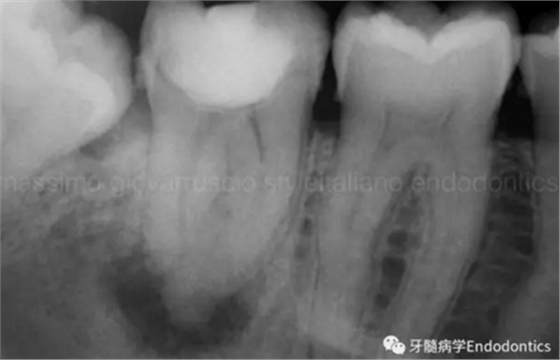

圖6.術(shù)后X線片顯示在根管機(jī)械預(yù)備后保留了原始的根管解剖形態(tài)結(jié)構(gòu)。冠方預(yù)敞和探查保證了對(duì)整個(gè)根管解剖形態(tài)結(jié)構(gòu)的保護(hù)。

圖7.具有解剖障礙的根管,比如根尖區(qū)不規(guī)則的直根管、存在不規(guī)則急彎的彎曲根管。

圖8.這個(gè)根管需要智慧和毅力才能越過(guò)。難點(diǎn)在于通過(guò)在觸覺(jué)(通過(guò)手用器械傳來(lái)的感覺(jué))感受到銼在根尖的阻力。這會(huì)發(fā)生是因?yàn)殇S的尖部會(huì)被不規(guī)則解剖形態(tài)干擾,而不是銼到全長(zhǎng)并超出。